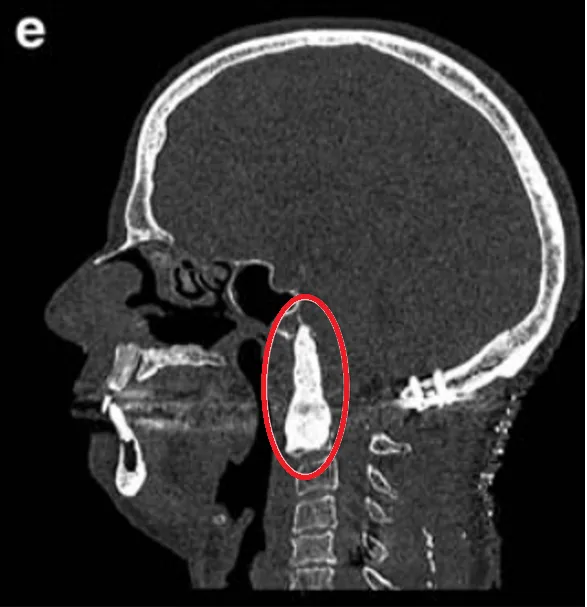

A和B:术前CT扫描显示颅颈交接区脊索瘤,侵犯斜坡-枕髁并呈溶骨性损害。C:术前MR显示肿瘤较大延伸,并浸润长入硬膜内的脑实质。D:术后CT显示PMMA枕髁重建稳定良好。E:术后三维CT显示C0-C3-C4-C5枕颈融合稳定,与根钉弯曲有利于PBRT治疗。F:术后MR显示全切肿瘤和脑干延髓占位压迫得到解除。